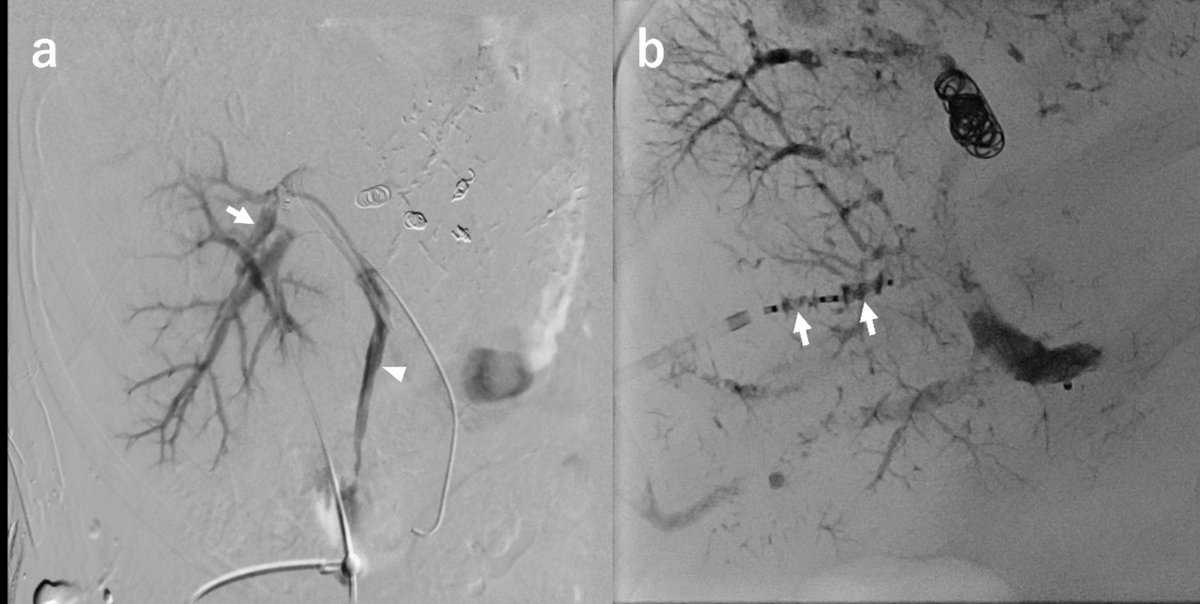

However, the strongest predictor of LTP remains the minimal ablative margin (MAM), while MRI serves as a valuable complementary tool within a multimodal approach to optimize outcomes.